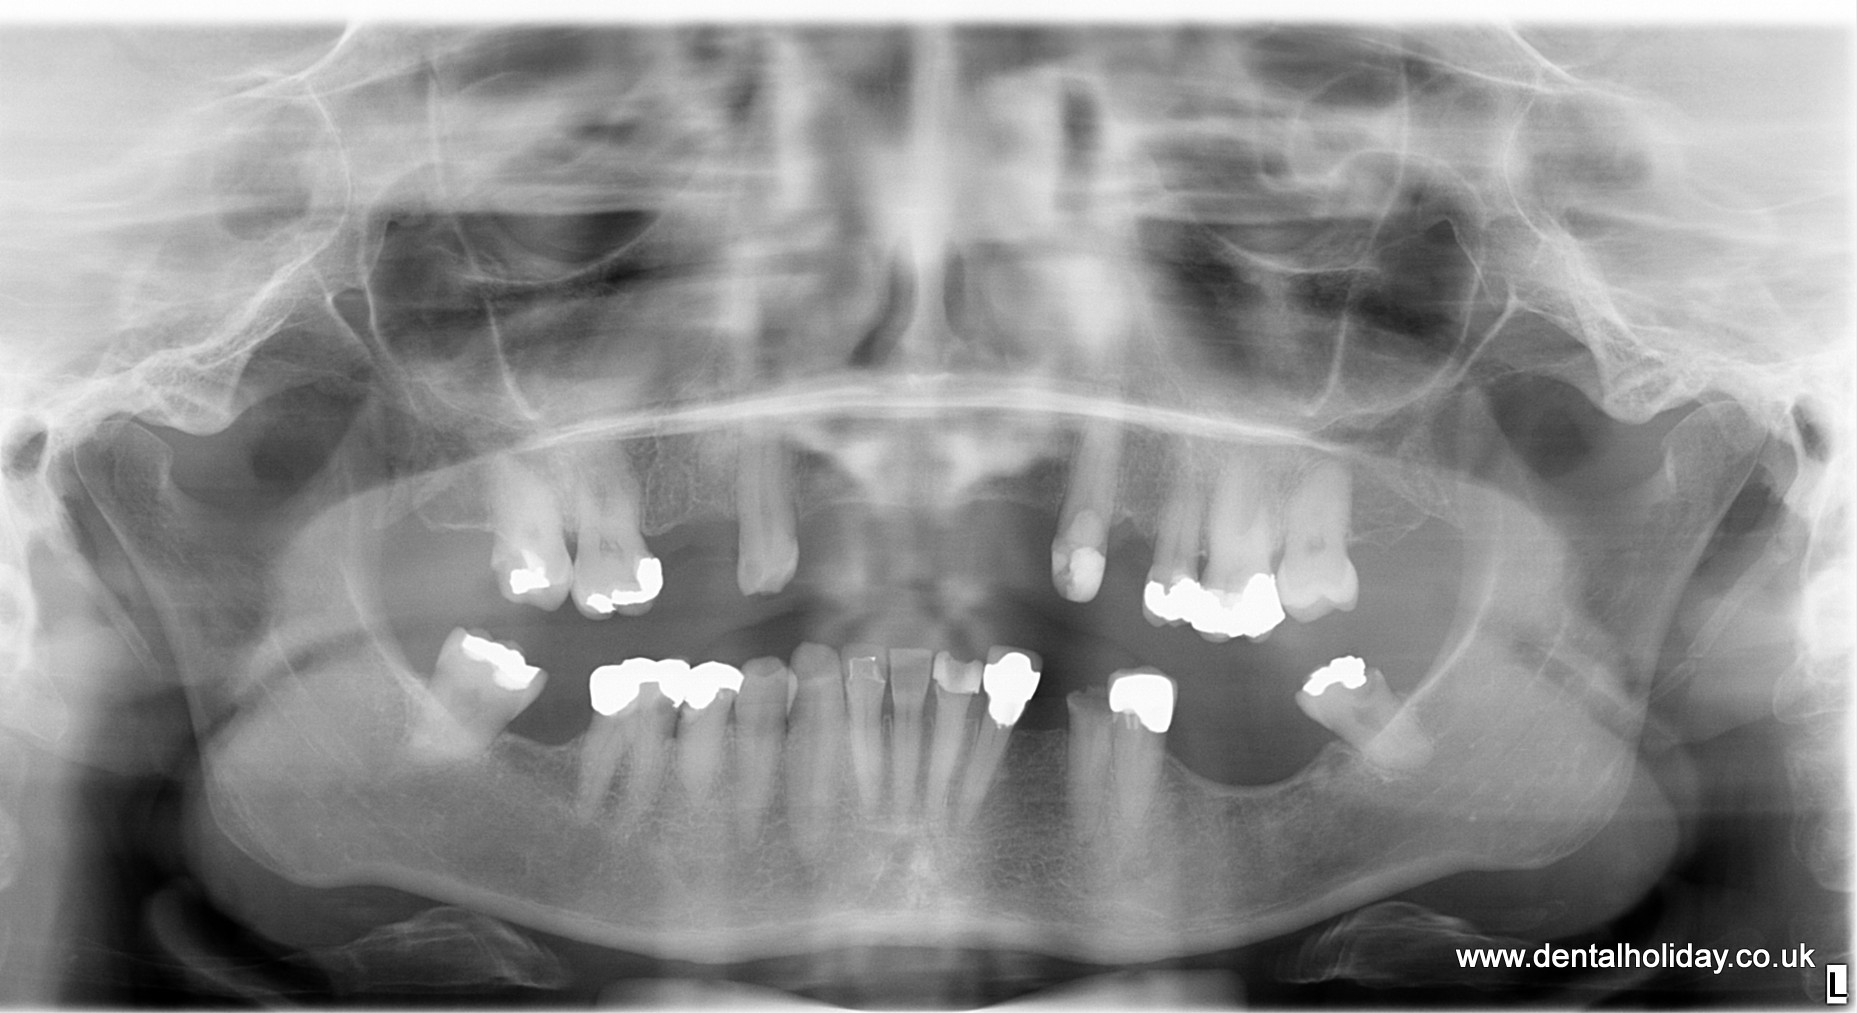

This case study details exactly how Janice’s dental treatment abroad progressed and here are the x-rays before and after for you to see before you read how the treatment progressed.

Janice wanted to have full upper and lower jaw replacement with dental implants, so Dr.Marek due to the weak bone structure that was present, planned to place 6 dental implants for her upper jaw and 6 dental implants for her lower jaw together with a 12 unit non-removable ceramic bridge fitted over upper and lower dental implants. The overall healing after the implant placement was advised for 3 months.